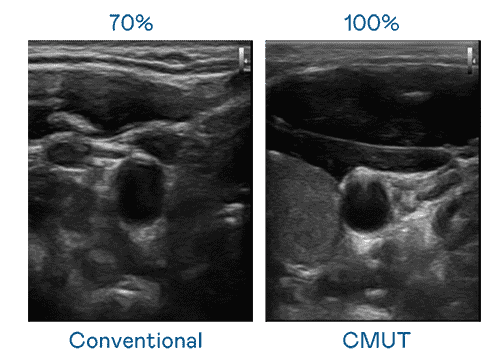

CMUT 技术是一种用电容式微机电元件来产生超音波讯号的技术。。与传统 PZT 压电式技术相比,,,,CMUT 频宽增加 30%,,更宽频的超音波讯号让影像解析度大幅提升,,是实现高影像品质医疗超音波扫描、、、、促进精准医疗发展的关键技术。。。。

大频宽带来超清晰影像

超音波影像的解析度高低,,,首先取决于探头能发出的讯号频宽。。。。MG电玩 CMUT 可提供高清晰的超音波讯号,,,,提供高频宽、、高灵敏度、、、、影像纹理细节更高的超音波影像,,,,协助医护人员缩短影像判读时间及利用精准的医疗影像进行诊断。。。